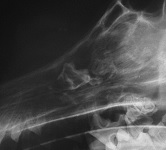

a) On the lateral radiograph a thick brush border perisoteal reaction is visible of the ventral

mandibular cortex. On the dorso-ventral view it appears as if the majority of the reaction is

situated just on one of the mandible and here a radiopaque mass is evident superimposed on the

mandibular 4th premolar and first molar teeth. The radiographic appearance, even being

unilateral, together with the signalment and history makes craniomandibular osteopathy the most

likely diagnosis. Unilateral disease should be differentiated from osteomyelitis, severe

localised periodontitis and neoplasia.